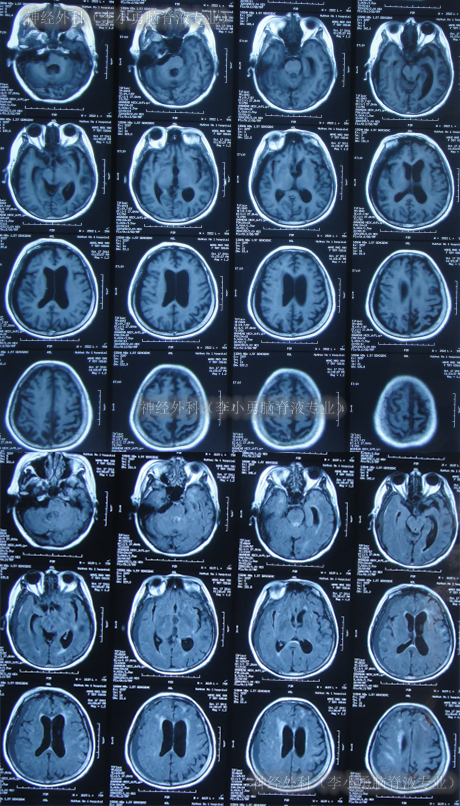

第2家医院出院1月余即2012年2月7日,夜里起夜突然又重复发作以前的症状(恶心呕吐、头昏),且比前2次发作严重,2012年2月8日住入第3家医院:呼和浩特市某三甲医院的神经外科治疗,入院查头颅CT(图-2)和MRI(图-3);脊髓核磁(图-4);肺部CT(图-5)及多次腰椎穿刺脑脊液化验检查(糖低、蛋白高),诊断为:结核性脑膜炎,脑积水。

图-2:2012年2月9日头颅CT